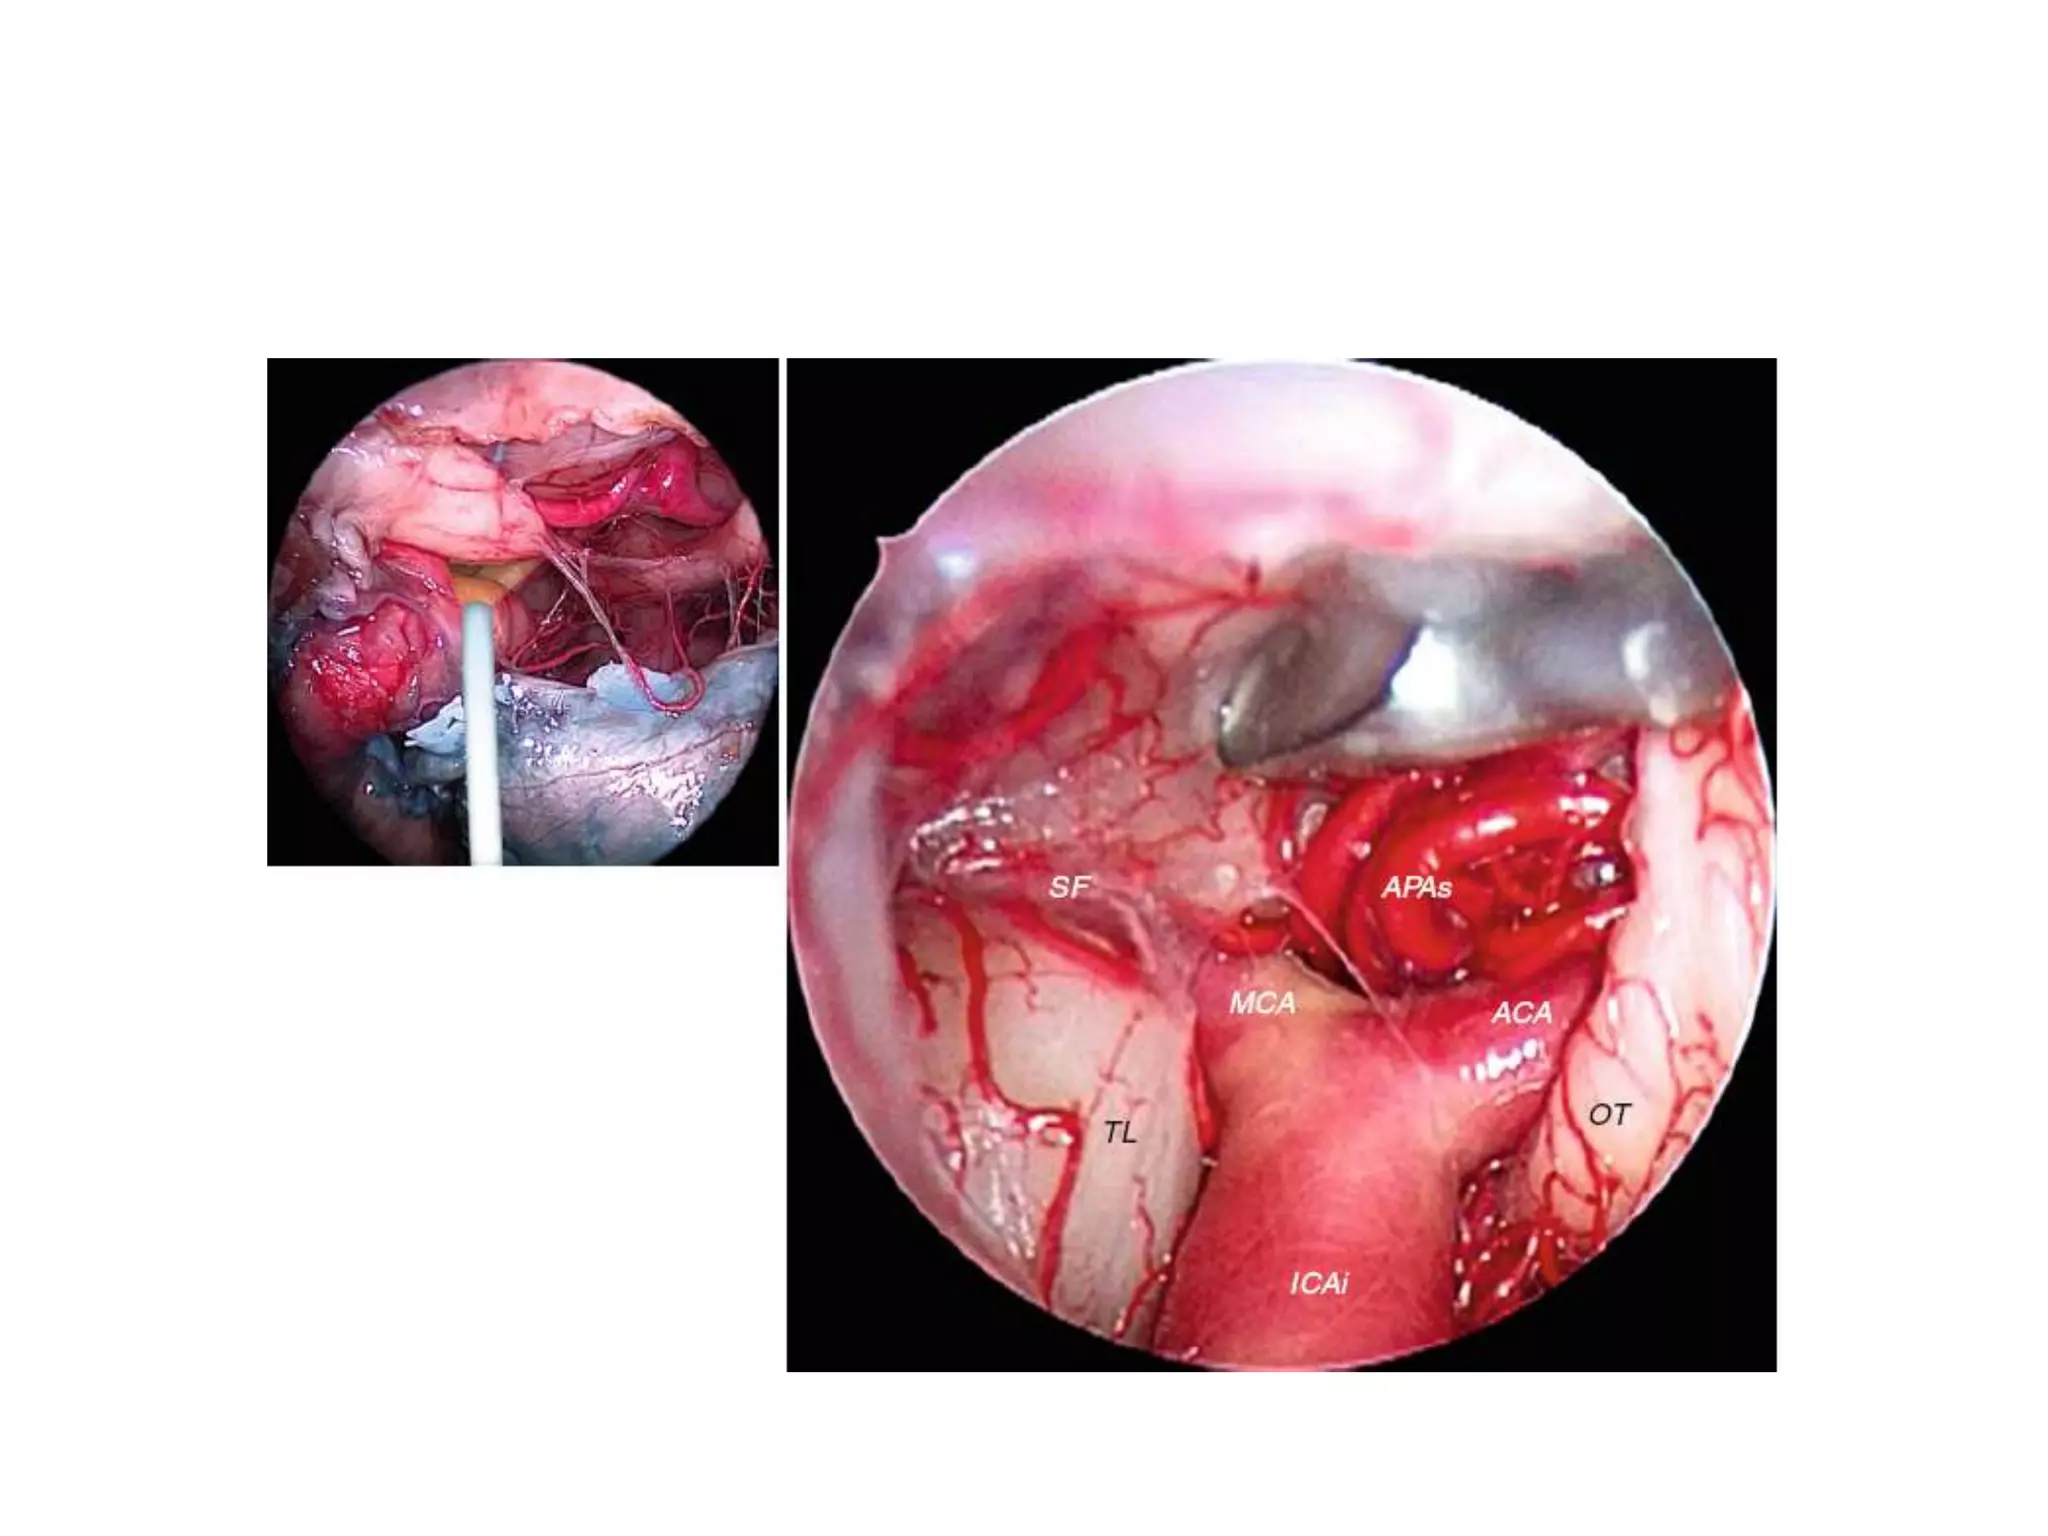

APAs anterior perforating arteries, ICAi intracranial portion of

the internal carotid artery, OT optic tract, SF Sylvian fi ssure,

ACA anterior cerebral artery, APAs anterior perforating arteries, FOA fronto-orbital artery,

FOV fronto-orbital vein, FPA fronto-polar artery, ICAi intracranial segment of the internal

carotid artery, MCA middle cerebral artery, OlfT olfactory tract, OlfV olfactory vein, ON optic

nerve, PS pituitary stalk, TL temporal lobe, black asterisk anterior communicating artery

ICA dividing into ACA and MCA

Optic tract [ OT ]

Fig. 4.8 Intradural exposure; right approach. Before (a) and after (b) opening of the

Sylvian fissure. A1 first segment of the anterior cerebral artery, AC anterior clinoid, FL

frontal lobe, HA Heubner’s artery, I olfactory tract, III oculomotor nerve, ICA internal

carotid artery, LT lamina terminalis, M1 first segment of the middle cerebral artery,

MPAs perforating arteries, ON optic nerve, P2 second segment of the posterior

cerebral artery, PC posterior clinoid, PcoA posterior communicating artery, SF sylvian

fissure, TL temporal lobe, TS tuberculum sellae